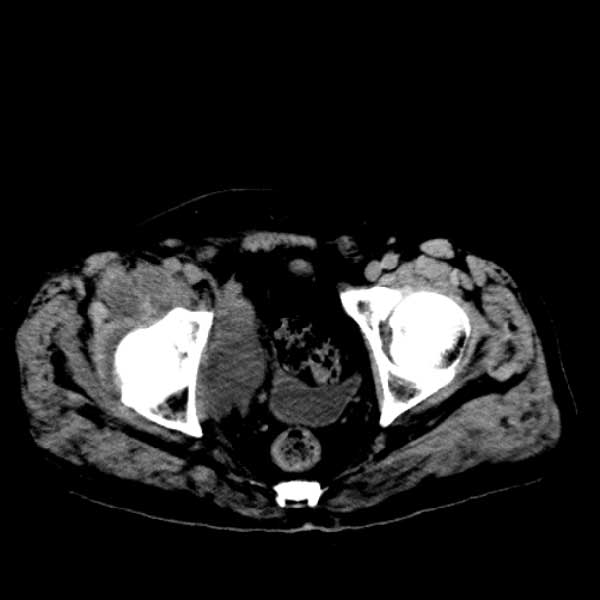

标题: CT13513:男 71 腹部疼痛20余天,近几天高热就诊,骨窗未见异 [打印本页]

标题: CT13513:男 71 腹部疼痛20余天,近几天高热就诊,骨窗未见异

考虑感染性病变可能性大,起源于阑尾?

考虑为化脓性阑尾炎.脓肿形成.及多肌肉累及.

考虑右侧腰大肌脓肿,向右髂窝、右腹股沟流注。

支持化脓性阑尾炎伴右髂窝脓肿、腰大肌腰方肌脓肿形成。

考虑腹腔及盆腔化脓性炎症,累及右侧髋关节及腹股沟区.

首先考虑化脓性阑尾炎伴腰大肌、腰方肌脓肿,不除外回盲部结核。

回盲部癌待排除。

患者肠镜检查考虑结肠癌,病理证实

患者肠镜检查考虑结肠癌,病理证实。肺部ct可见多发结节,考虑转移